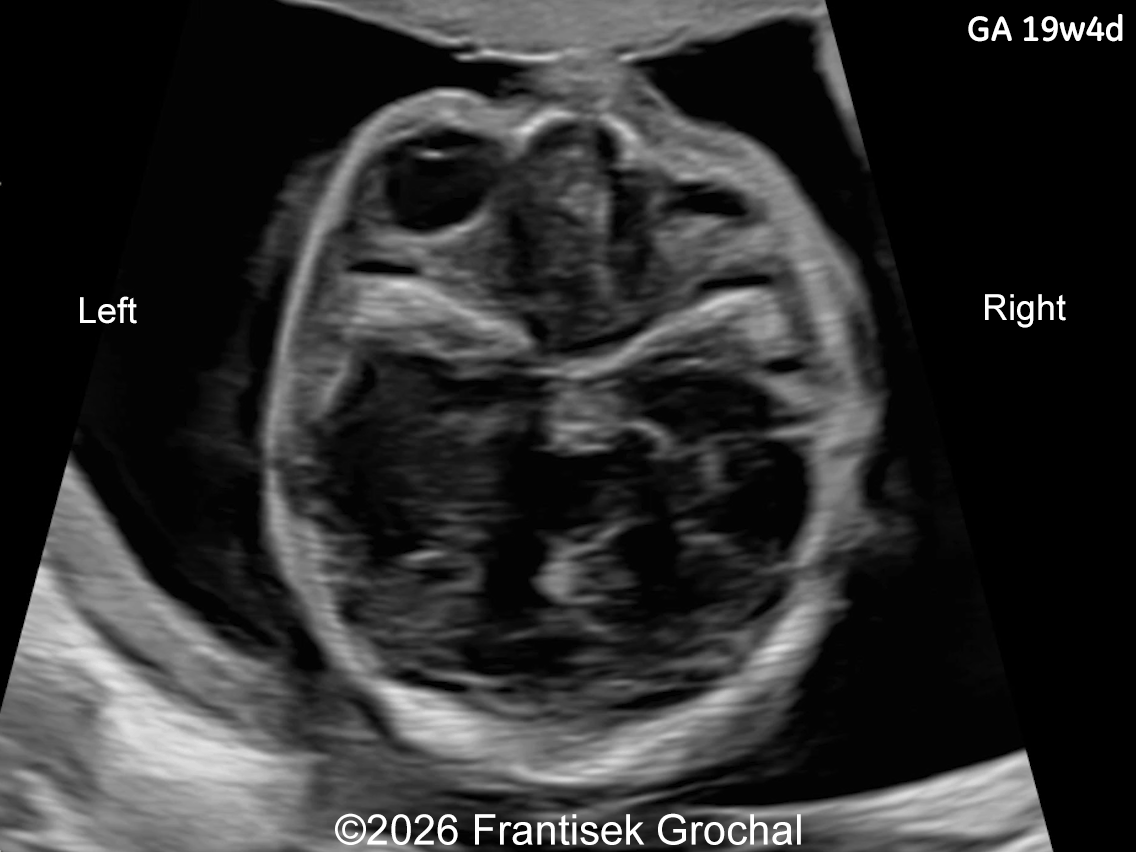

19+4 weeks of gestation; transverse view through the fetal orbits demonstrating right-sided microphthalmia.

Image 2 19+4 weeks of gestation; transverse view through the fetal orbits demonstrating right-sided microphthalmia.